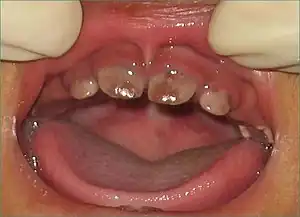

| Brown discoloration of the teeth caused by porphyrin accumulation which will fluoresce under Wood's lamp (Erythrodontia). | |

Though expressivity is varied depending on the mutation responsible for decrease in enzyme function, severe cutaneous sensitivity is present in most cases of this Porphyria. An estimated 30–40% of cases are due to the C73R mutation, which decreases stability of the enzyme and results in <1% of its activity.[9] Exposure to long-wave ultraviolet light causes the affected skin to thicken and produce vesicles that are prone to rupture and infection; these secondary infections, along with bone resorption, can lead to disfigurement of the sun-exposed face and extremities.[10] Enzyme dysfunction prevents the normal production of heme and hemolytic anemia is another common symptom, though a lack of hemolysis in this disease is possible. Porphyrins additionally accumulate in the bone and teeth, resulting in erythrodontia.[10][11] When unexpected attacks occur, abdominal pain, as well as vomiting and constipation commonly follow the attacks. Exposure to the sunlight can cause discomfort and result in blistering, consciousness of heat, and swelling and redness of the skin.[12]